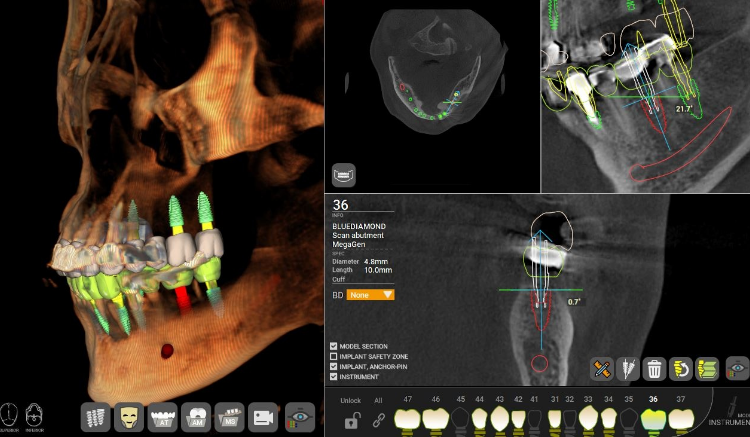

• Computer-Guided Implant Treatment

No margin for error.

Computer-guided implant treatment utilizes 3D diagnostic systems

and virtual surgery to determine the optimal implant position.

Because implant fixtures, customized abutments, and prosthetics are fabricated

in advance, this method ensures accurate and efficient treatment.

• #Precision Implant

• #Computer-Guided Treatment

• #Customized Implant

• #Accurate and Efficient